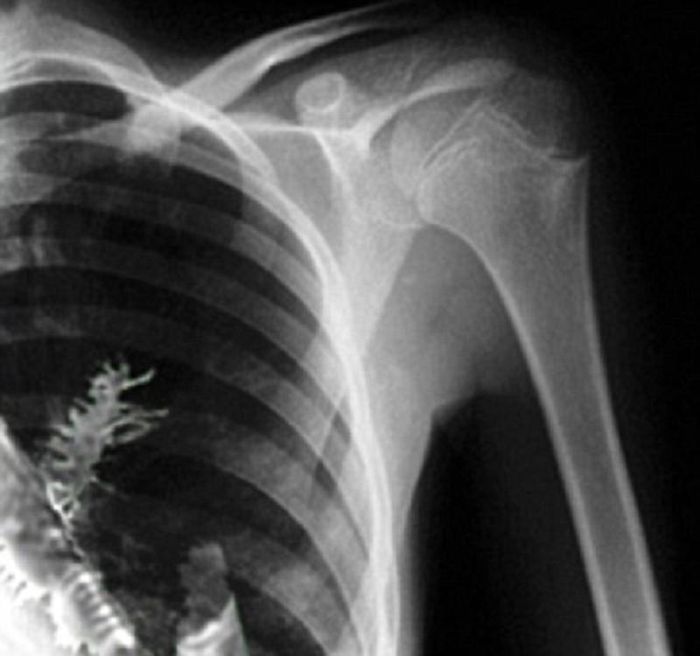

Phim X-quang chụp cây linh sam mọc trong phổi anh Artyom Sidorkin.